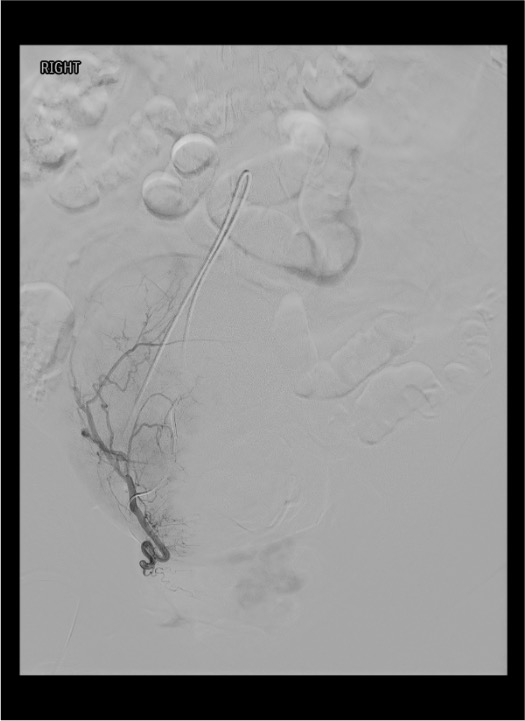

Embolization — Right Uterine Artery

Angiographic Landmarks

Uterine Artery Identification

- IIA angiogram: uterine artery courses medially from the anterior division toward the midline pelvis

- Characteristic “hook” or “U-turn” as it crosses over the ureter and turns superiorly along the lateral uterus

- Fibroids demonstrate a dense vascular blush on arterial phase — confirms fibroid vascularity and supply from this uterine artery

Critical Branch Points

- Cervicovaginal branch takeoff: arises from the uterine artery early in its course; supplies cervix and upper vagina; must embolize DISTAL to this branch

- Ovarian artery collateral supply: look for retrograde filling of ovarian artery at the fundus on late-phase images; if prominent, consider aortogram to evaluate for accessory ovarian artery supply requiring separate embolization

- Anastomotic arcade: ascending uterine artery connects with descending ovarian artery at the fundus — this is the route for potential non-target ovarian embolization